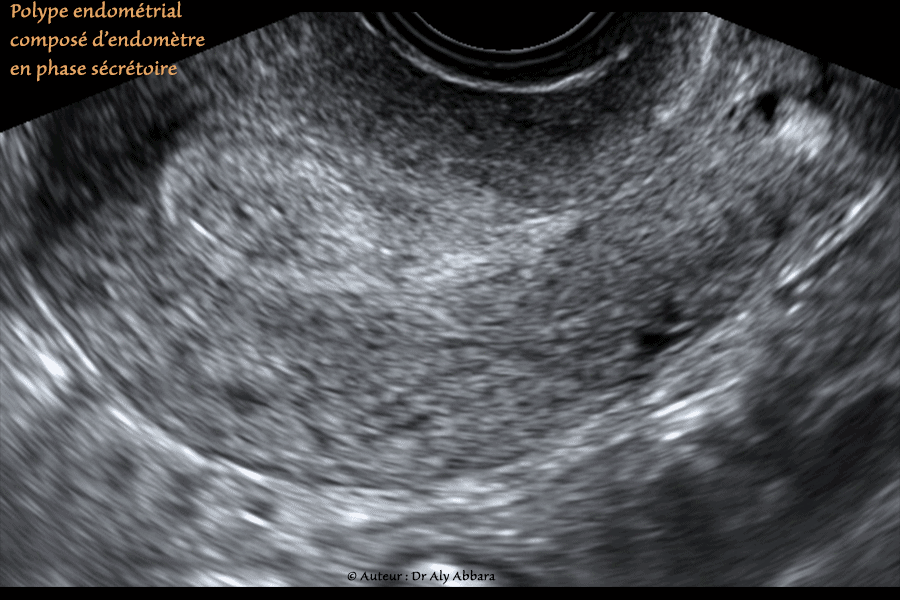

• Images échographiques montrant (sur des coupes sagittale, transverse et frontale), dans la moitié gauche du fond de l'utérus, la présence d'une formation polypoïde mesurant environ 18 x 10 x 24 mm (soit 2,3 cm3).

L'endomètre lors de la réalisation de cette échographie était en phase sécrétoire (24° jour du cycle menstruel) : endomètre hyperéchogène et homogène sur la totalité de son épaisseur.

Le polype endométrial est de forme ovoïde de structure échographique identique à celle de l'endomètre.